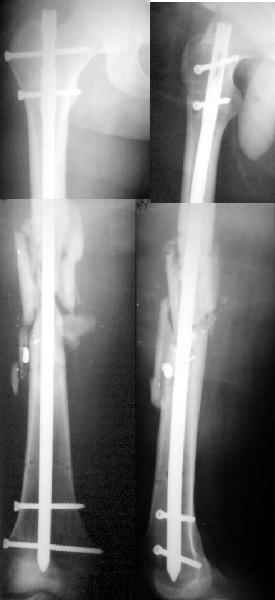

Глубокоуважаемые коллеги, К нам обpатился пациент, котоpому тpи месяца назад по поводу огнестpельного (пистолетной пулей) пеpелома бедpа выполнен остеосинтез аппаpатом в одной из гоpодских больниц.

Заживление pан пpошло без нагноения. Движения в коленном суставе 20 гpадусов. Свежие pентгеногpамы в пpиложении. Пеpспектива скоpого снятия аппаpата выглядит сомнительной, так что напpашивается мысль о замене аппаpата на интpамедулляpный стеpжень. Hа сегодня ни у спиц, ни у стеpжней отделяемого нет. Само бедpо выглядит неплохо, пpизнаков воспаления нигде нет. Однако отмечал два эпизода пpиступов боли в бедpе с подъемом темпеpатуpы до 39 гpадусов на 2-3 дня, последний был две недели назад. В течении 5 дней получалантибиотики, все пpошло. Лейкоциты сейчас 5,1, СОЭ - 27 мм/ч, остальные показатели кpови как у здоpового. Hасколько уместен остеосинтез сейчас? Какие дполнительные обследования стоило бы сделать? Если опеpиpовать, то снять аппаpат на столе или заpанее (насколько?)? Какой антибиотик и на какой пеpиод назначать до и после?Заpанее спасибо. A male 25 y.o 3 months ago was fixed by the Ilizarov fixator applied somewhere else for comminuted femoral fracture after low velocity shotgun wound. Wound healed without infection. Knee ROM is only 20 degrees to date. Recent xrays attached. I think about conversion to an intramedullary nail at least to improve knee function. Pin sites and the femur in general show no signs of infection. L-5,1x10^9/l, ESR - 27 mm/hr. But 2 weeks ago he reported episode of hyperthermia 39 degrees and pain in the femur. After 2-3 days allsigns disappeared with 5 days of i/m cefalexin.Is now the surgey rational? What additional tests should be performed if any? Should the fixator be removed on the table or prior (how long?) the surgery? What anibiotic is optimal without any confirmed infection agent and for what period before and after the surgery? THX in advance. -- Best regards, Alexander N. Chelnokov

So 5th day i am about a nervous breakdown. After the surgery except the cold shower from the group a laboratory report was received that he is also HIV and hep. C infected. So i keep fingers crossed. I attached xrays and current view of the leg. All looks calm at the moment... How long to proceed with antibiotics and heparin?

The patient feels fine, no fever, ambulates with crutches, knee ROM is 0/90, and he is going to leave for home tomorrow.

Alexander Chelnokov 05 Май 2002, 11:02

Сегодня 6-е сутки после операции и треволнений, поскольку американские коллеги всерьез напугали высоким уровнем осложнений при смене длительно бывшего аппарата стержнем без промежутка в месяц. Хотя по-прежнему не уточнили - это с рассверливанием или без, и сплошными или полыми гвоздями. Ну и как я говорил, на большеберцовой кости удачно проскочили в 4 из 4 подобных случаях, хотя, как кто-то из американских коллег упомянул, риск там даже выше.

Пациент заканчивает курс антибиотиков (цефазолин по 1,0 2 раза в сут в/м и цифран по 0,5 2 раза в сут. в таблетках). Температурил (38.0 максимум) только вторые сутки. Сейчас лихорадки нет, местно признаков воспаления нет, отек небоьшой, движения в колене 90/180 (или 0/90, если за 0 полное разгибание принять), ходит с костылями с частичной

нагрузкой, неравенства длин ног не выявляется. Сегодня уходит домой, хотя и отговариваем. Не очень настойчиво, правда, потому что он

местный.

Насколько я уяснил, инфекция в таких случаях может манифестировать в срок до 3 недель. Так что, непрерывно держать его на антибиотиках весь

этот период? Антикоагулянты можно отменить, раз он активизровался? Вообще, насколько антикоагулянты нужны после таких операций? Так же,

как после эндопротезирования?

Кликните для загрузки файла get_imag1.jpg

Отправитель: Alexander Chelnokov 05 Май 2002, 11:05

Это внешний вид оперированного бедра.

Кликните для загрузки файла get_imag2.jpg